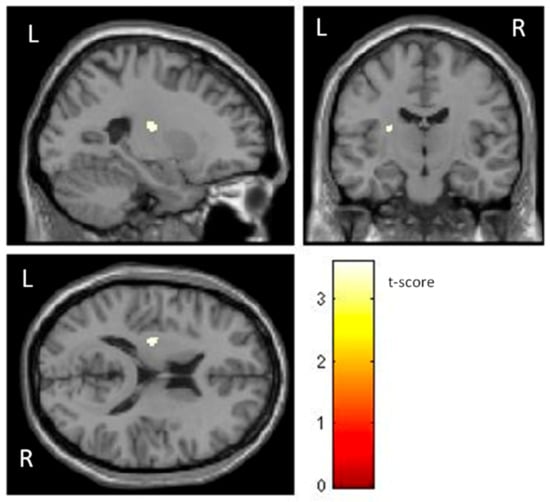

Significant differences between with and without phobia groups appeared in total GMV (group with phobia: mean = 673,26 cm3, SD = 70.85 cm3; group without phobia: mean = 718.81 cm3, SD = 62.49 cm3, F1,60 = 7.20, p = 0.009). Total GMV correlated negatively with SR scores (r = −0.384, p = 0.002). ANCOVA revealed no significant effects of SR or age and did not exceed the cut-off point for considering them statistically significant (F1,60 = 33.56, p < 0.05). The whole-brain voxel-wise analysis showed that, compared with individuals without phobia, individuals with phobia had significantly smaller GMV in the right insula (t (60) = 5.18, p < 0.001); a cluster of right lateral, anterior, and inferior OFC (t (60) = 4.98, p < 0.001); a cluster of left posterior, medial, and lateral OFC, and left insula (t (60) = 4.86, p < 0.001); and a cluster of left superior medial frontal, right superior frontal, and right ACC (t (60) = 4.48, p < 0.001) (Table 1 and Figure 1). In all contrasts, the effect size was moderate.

Figure 1. Significant differences in GMV of brain regions between non-fearful controls (larger) and individuals with phobia (corrected with Gaussian random field theory with a significance threshold of a voxel-wise value of p < 0.001 and cluster probability of p < 0.05).